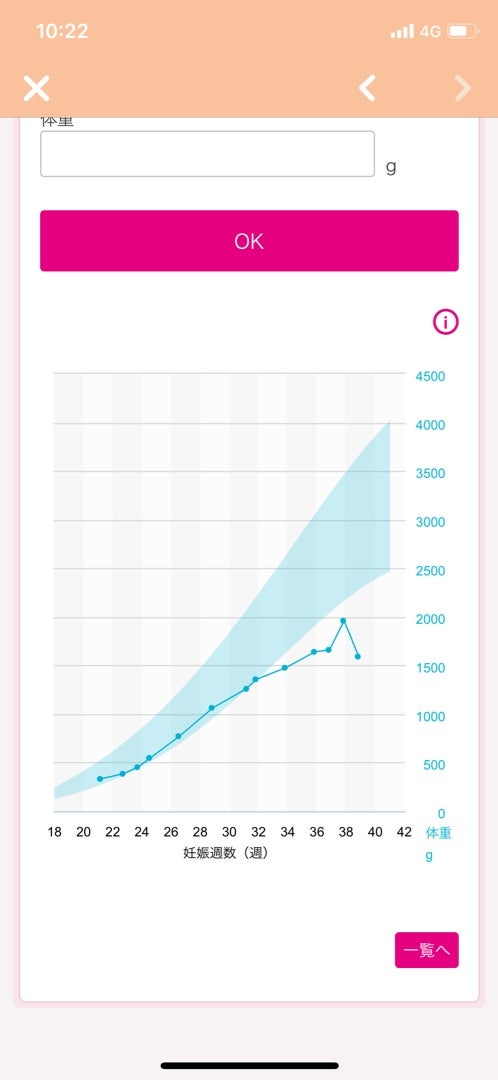

母子手帳「胎児発育曲線 新生児の成長曲線 」の見方と活用法-おむつのムーニー 公式 ユニ・チャーム。

胎児発育曲線ギリギリ成長の小ささで16週から34週まで育ってるべびお君。 - 保育士うたのサイト。

母子手帳「胎児発育曲線 新生児の成長曲線 」の見方と活用法-おむつのムーニー 公式 ユニ・チャーム。